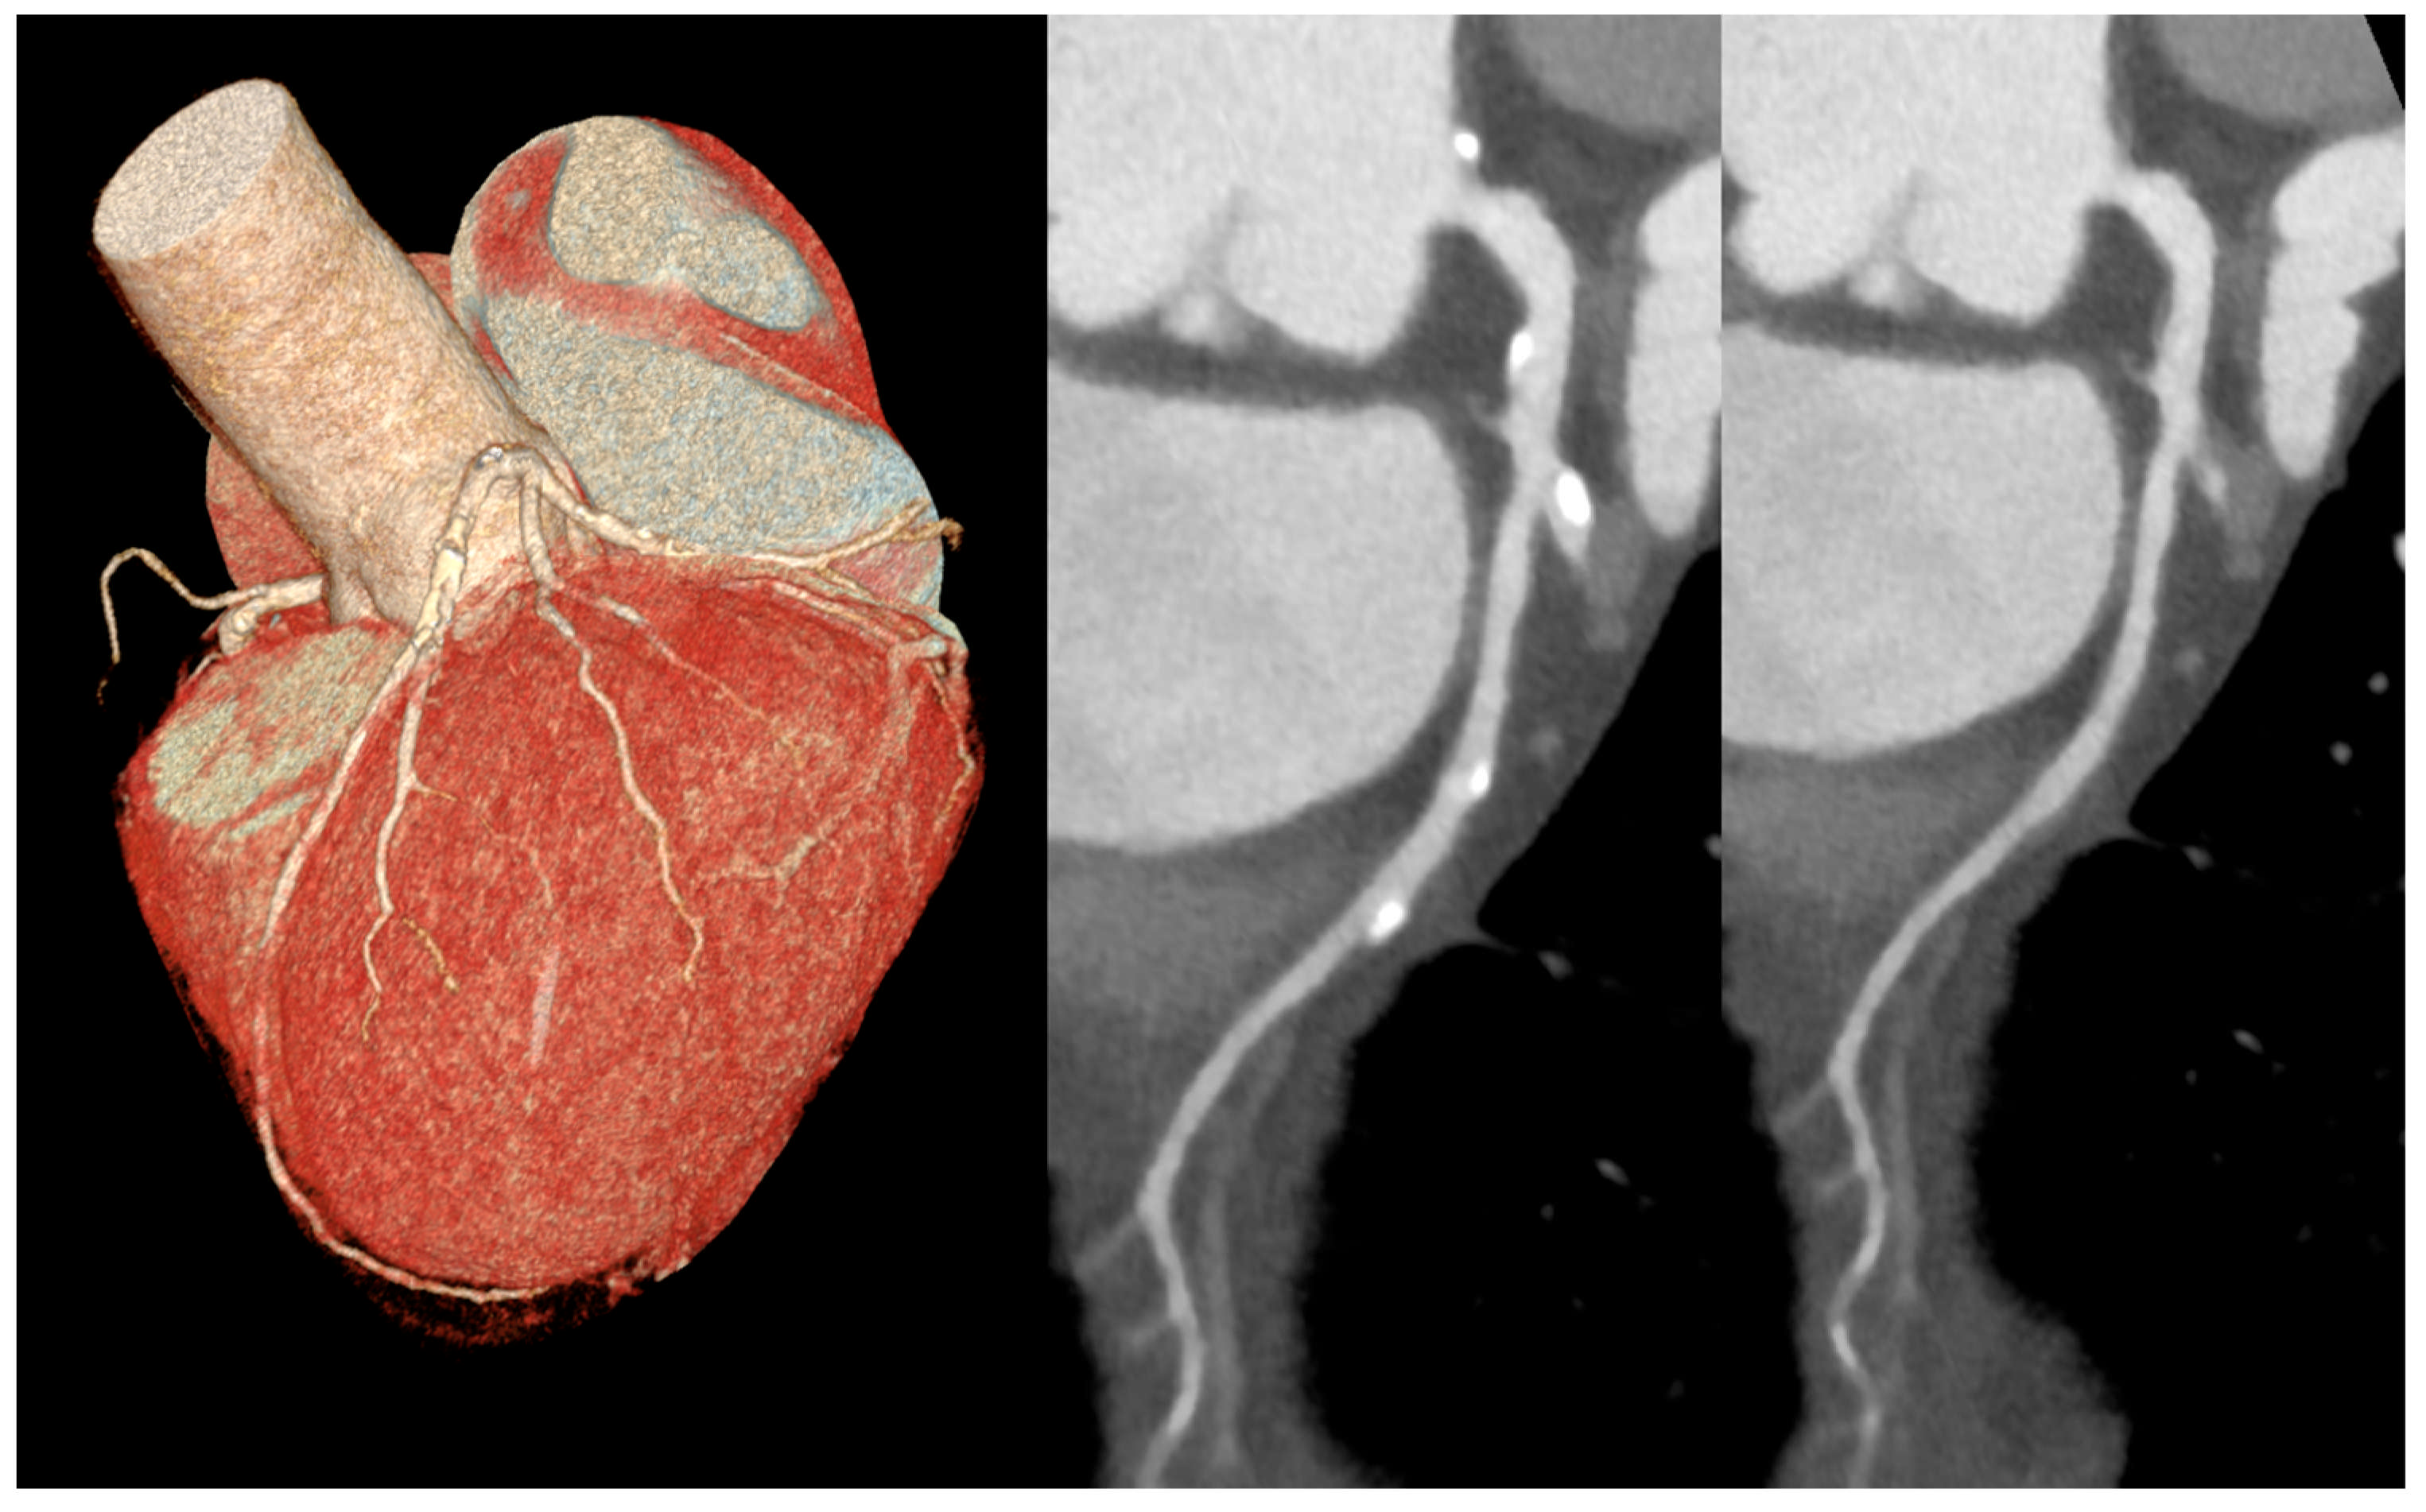

- Mergen, V.; Eberhard, M.; Manka, R.; Euler, A.; Alkadhi, H. First in-human quantitative plaque characterization with ultra-high resolution coronary photon-counting CT angiography. Front. Cardiovasc. Med. 2022, 9, 981012. [Google Scholar] [CrossRef] [PubMed]

- Halfmann, M.C.; Bockius, S.; Emrich, T.; Hell, M.; Schoepf, U.J.; Laux, G.S.; Kavermann, L.; Graafen, D.; Gori, T.; Yang, Y.; et al. Ultrahigh-Spatial-Resolution Photon-counting Detector CT Angiography of Coronary Artery Disease for Stenosis Assessment. Radiology 2024, 310, e231956. [Google Scholar] [CrossRef] [PubMed]